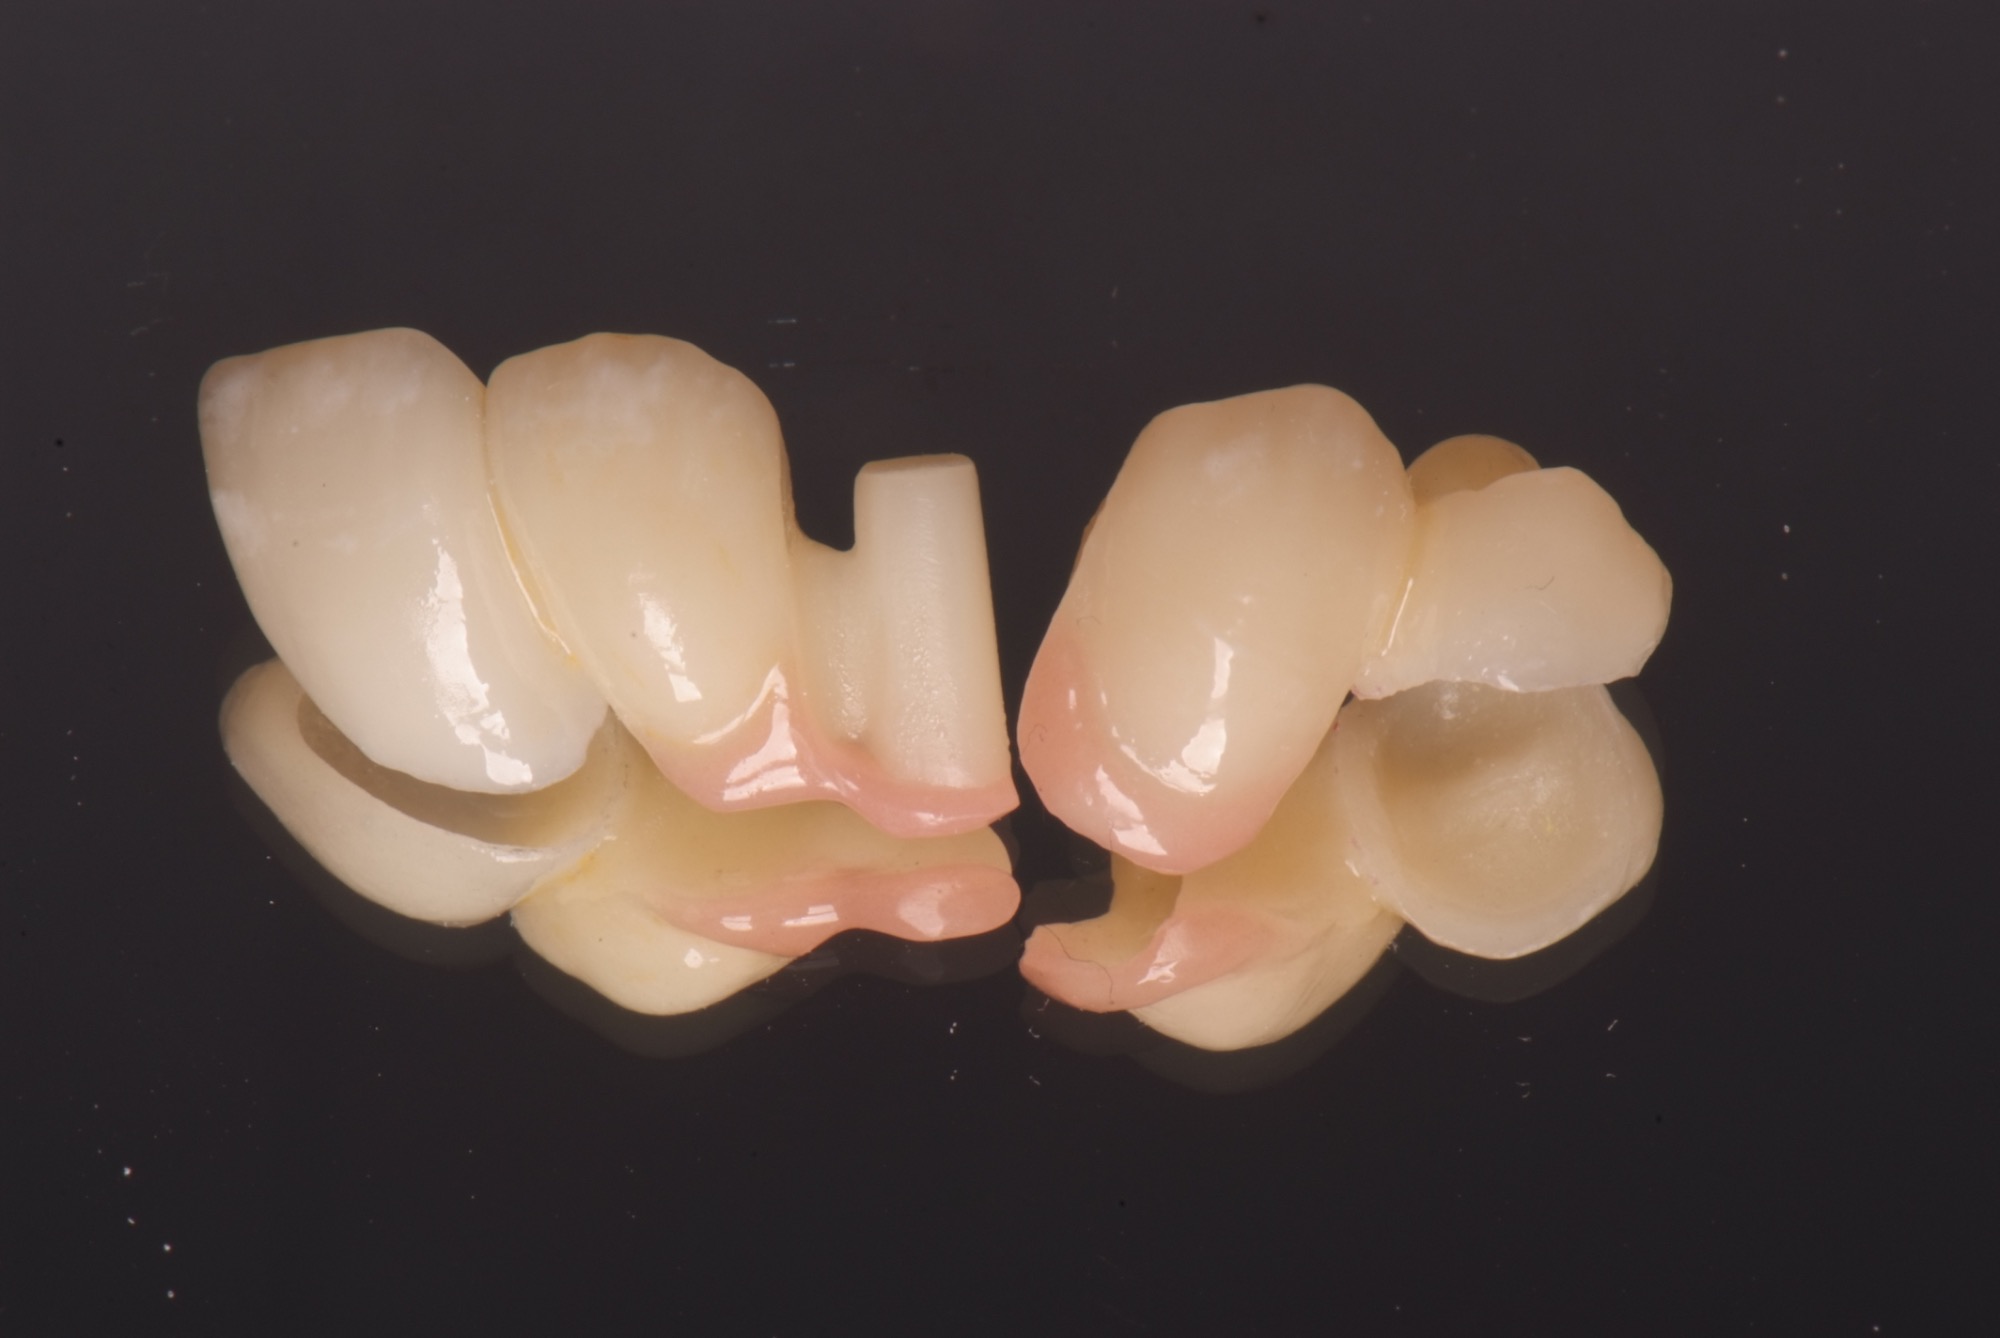

Veneerversorgung mit non-invasiven Veneers zur Verbesserung der Ästhetik.